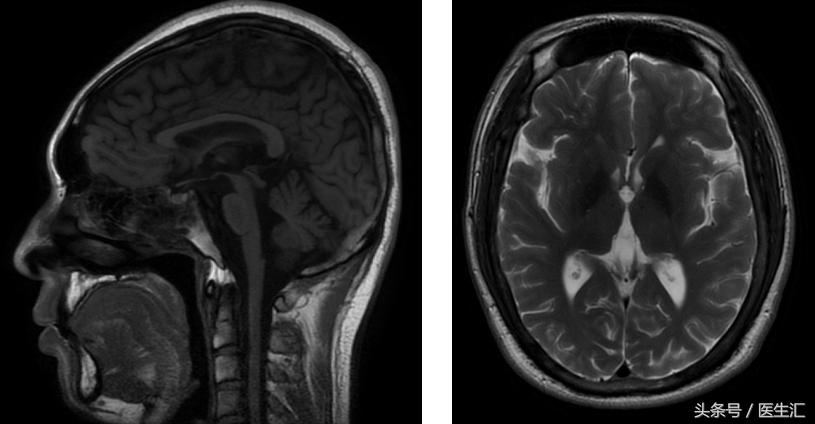

图像资料

核磁:小脑萎缩、脑干萎缩

定位:锥体外系(震颤)、小脑(步态、共济运动、影像学)